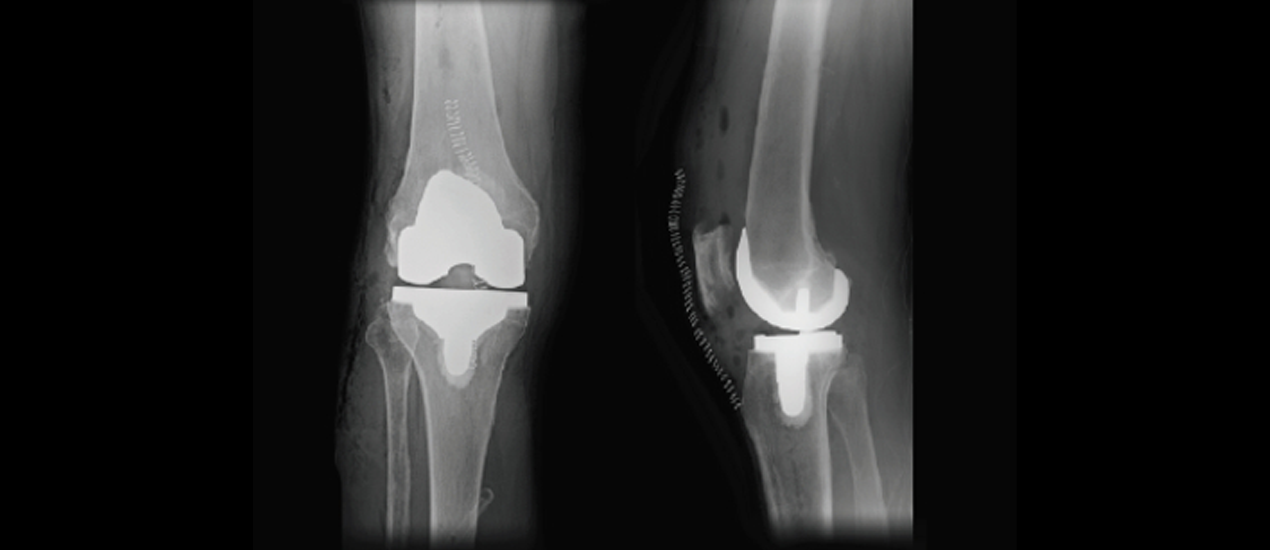

Catherine Cahill MD is at the forefront of orthopedic medicine, offering expert hip and knee surgical care to the community of Houston. As an esteemed Hip & Knee Orthopedic Surgeon, Dr. Cahill combines cutting-edge techniques with a compassionate approach to patient care, ensuring that each individual receives tailored treatment plans designed for optimal healing and recovery. For those contemplating knee surgery in Houston, Dr. Cahill's practice is synonymous with excellence and attentive care throughout every stage of the surgical process – from initial consultation to postoperative rehabilitation support. By focusing on innovative solutions and personalized attention, she commits herself fully to helping patients regain their freedom of movement without pain or limitation. If you're looking for reliable and skillful orthopedic services, look no further than Catherine Cahill, MD, where you'll find not just a surgeon but also a partner in your journey toward better joint health and improved well-being.